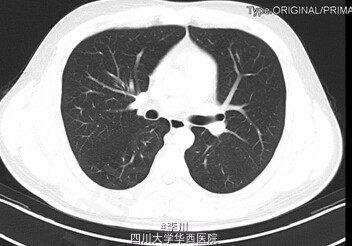

心肺腹查体无特殊。双侧手掌及足潮湿明显。胸部CT无特殊异常。